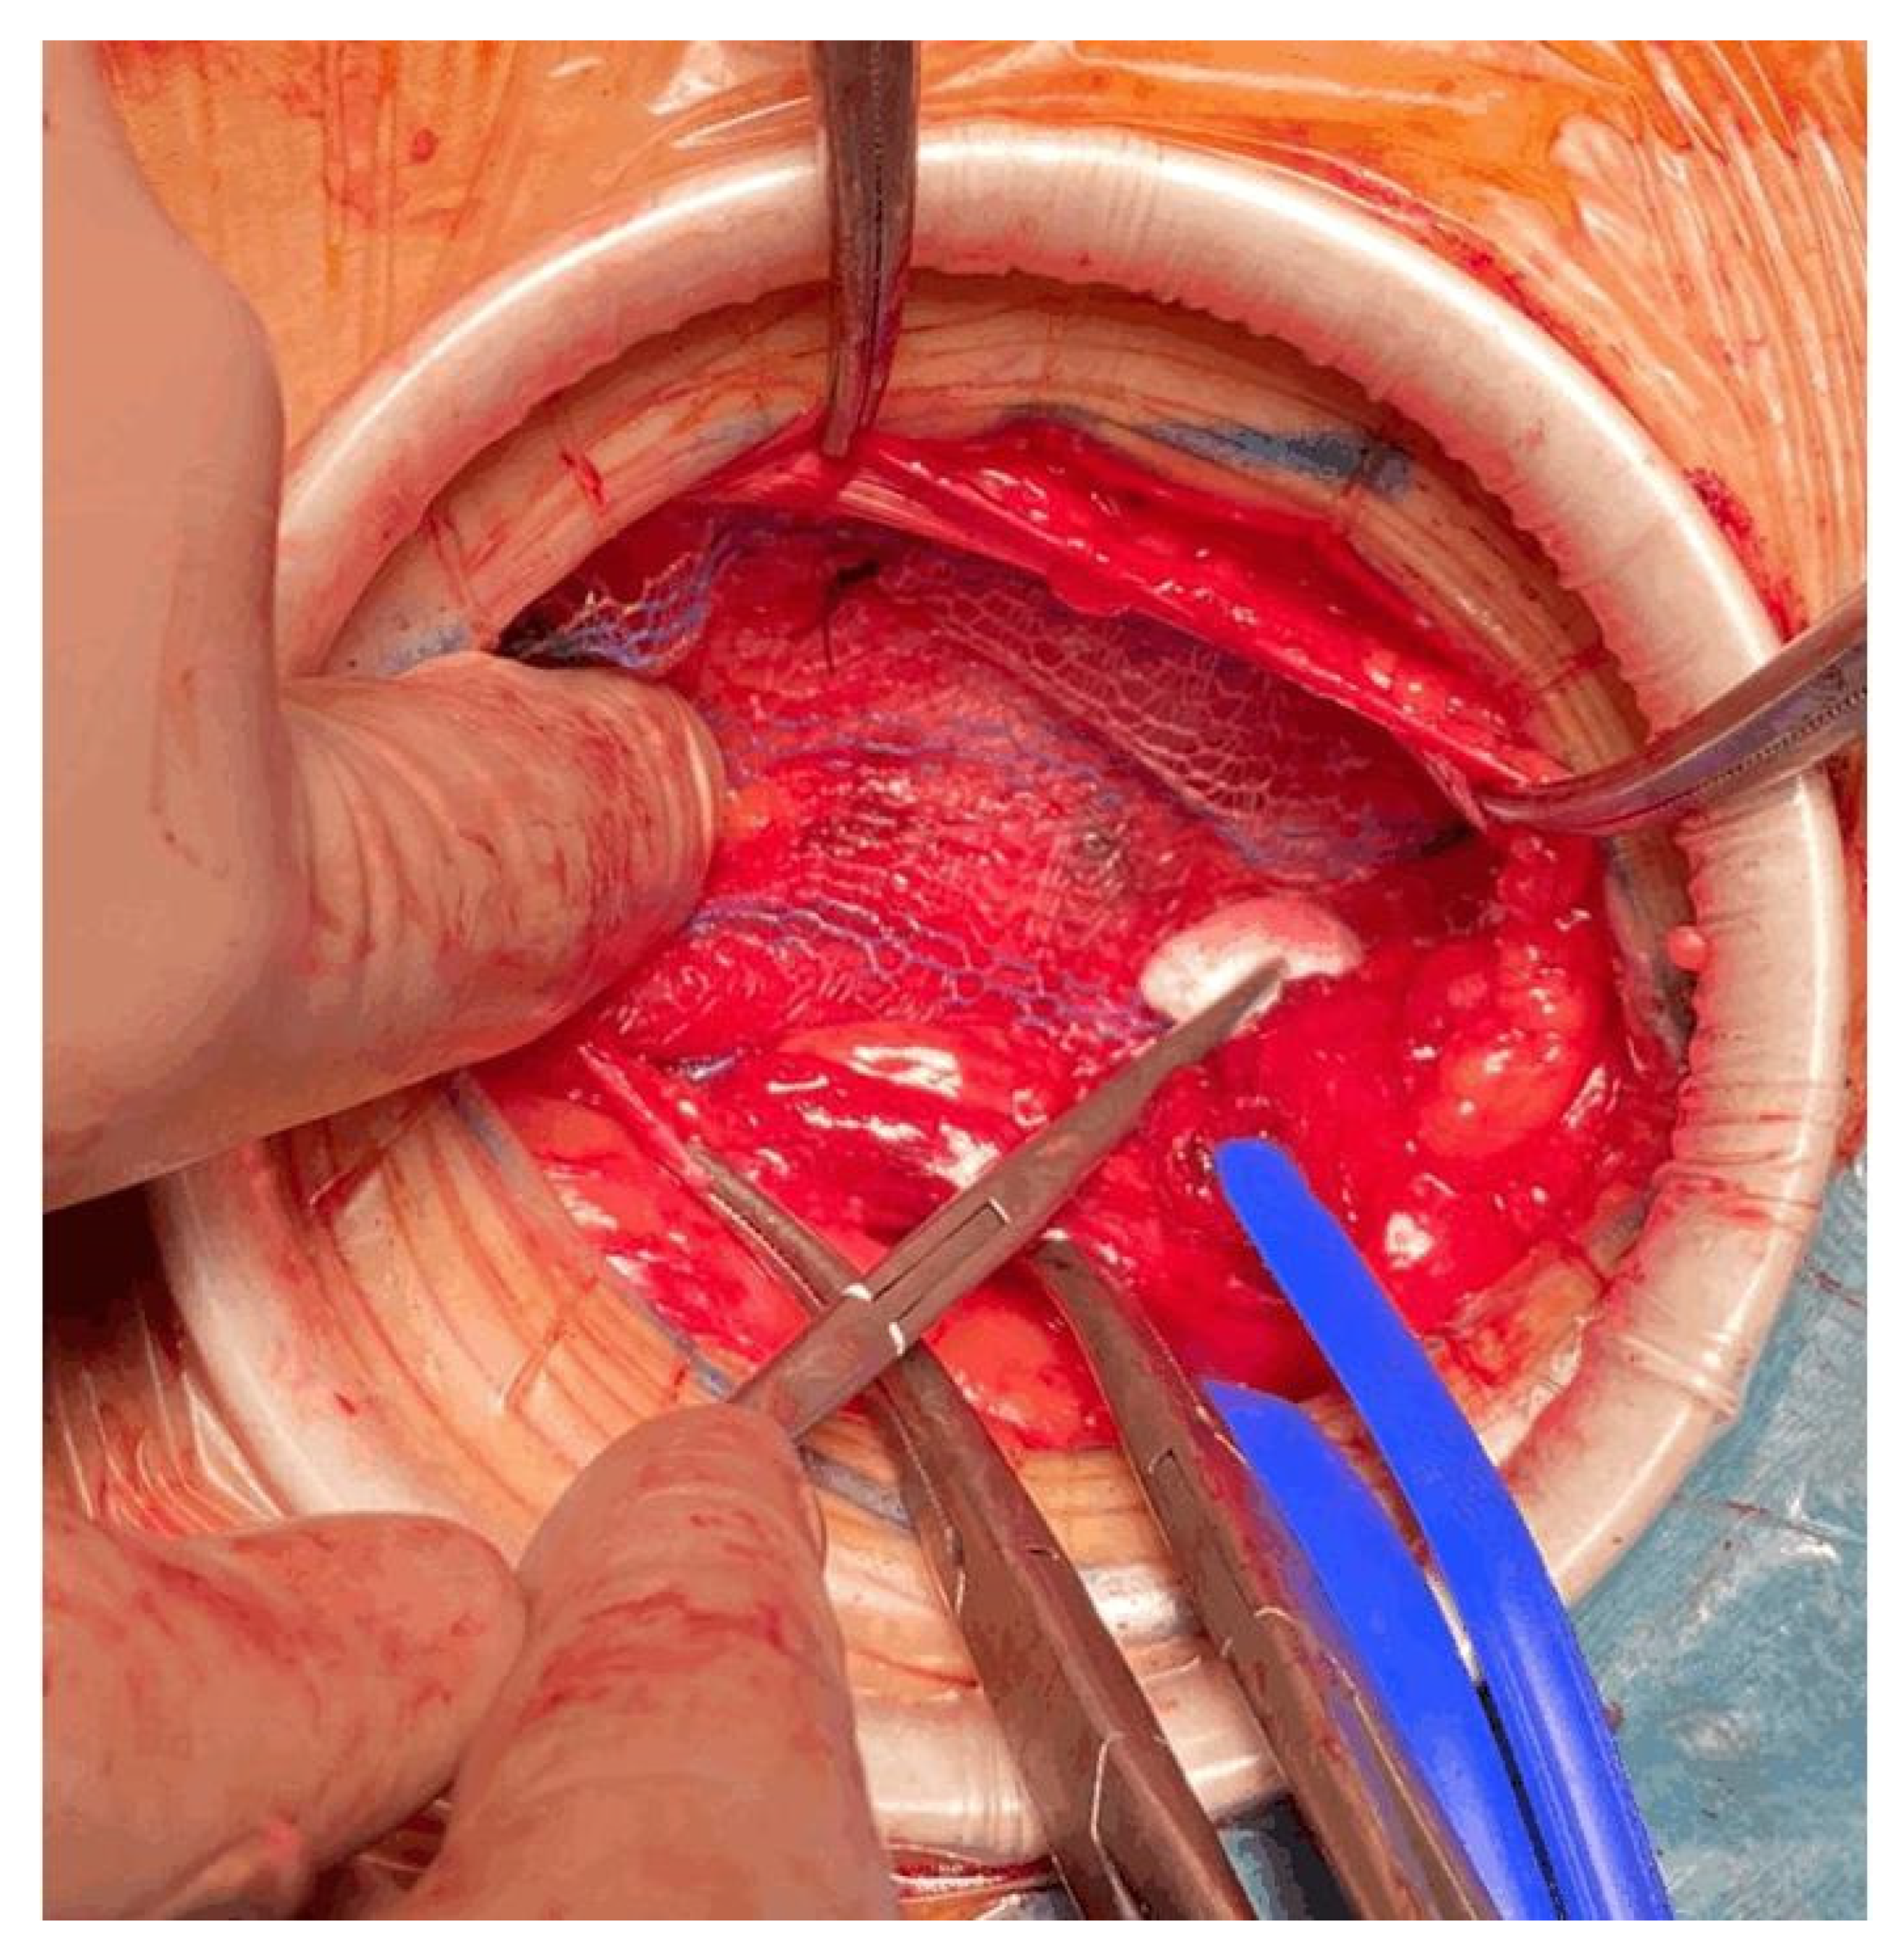

Anesthesia alone may not be adequate to control pain during hernia repair. One of the main causes of pain is traction. Traditionally, adequate surgical exposure has been accomplished with the aid of self-retaining retractors or by extending the incision length. Self-retaining retractors can lead to potential complications, including local tissue ischemia and pain.

To reduce traction during hernia repair, we used the Alexis™ S wound retractor. It provides 360 degrees of atraumatic circumferential retraction. The wound protector is placed after the incision of Scarpa’s fascia, exposing the aponeurosis of the abdominal external oblique muscle. With their index finger, the surgeon creates space towards the testicle, and then the surgeon places the Alexis™ S wound retractor, as seen in Figure 8 and Figure 9.

Figure 9.

Improved surgical exposure using wound retractor during mesh fixation.

The wound protector provides a significant increase in surgical exposure compared to self-retaining retractors. The wound protector reduces the depth of the operative site, and it is helpful in obese patients. The reduction in traction improves postoperative pain due to the lower compressive force.

Several studies have reported the decreased rates of SSI even in clean wounds such as elective inguinal hernia repair [18,19,20].